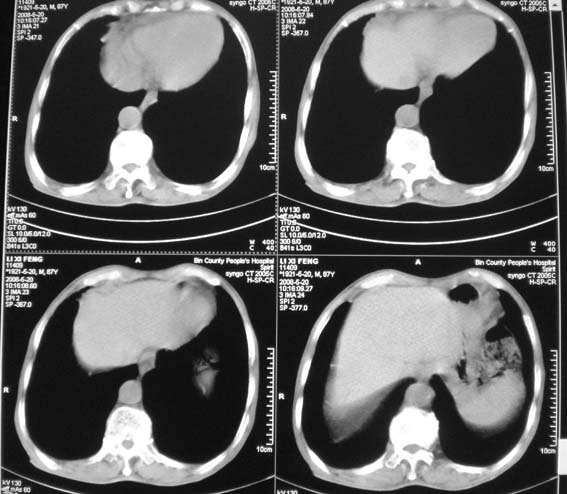

男,87岁,咳嗽、发烧、有黄痰,胸片示肺结核。

右肺上叶尖后段片状不规则致密影,密度欠均匀,相邻胸膜肥厚,纵隔内见多发肿大、钙化淋巴结,考虑为结核,部分坏死

有低密度坏死灶;结合痰检。